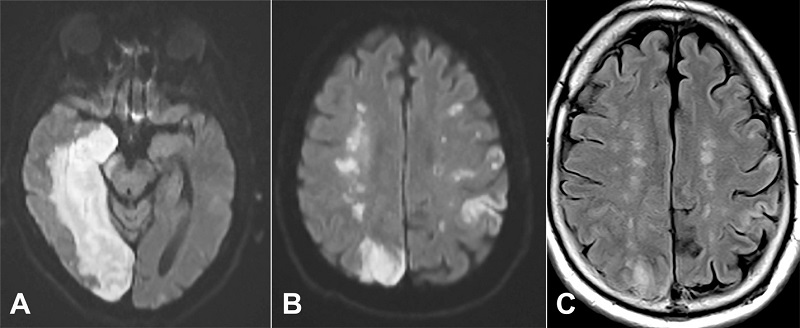

Four days later, the patient developed a new right hemispheric disease and was found to have a new large acute infarct of the right posterior cerebral artery territory (Figure 1). Bilateral deep white matter ischemic changes were also identified with a beaded, “rosary-like” pattern tracking along the internal watershed zone of the right corona radiata in extension from the adjacent PCA infarct (Figure 1). Despite medical intervention, the patient died approximately a month following admission.

The case presented here provides radiologic and post-mortem documentation of an evolving IWI. Similarly to the patient’s reported clinical history, cardiovascular disease, and proximal carotid atherosclerotic disease are important risk factors for the development of internal watershed infarcts in addition to diabetes mellitus; however, smoking and hypertension have not been independently associated with IWI when compared to general stroke patients in one retrospective study.1 The pathogenesis of IWIs is thought to be secondary to hemodynamic instability and severe hypoperfusion,4-5 and the current findings support this hypothesis, showing bilateral white matter ischemic changes as well as right hemispheric IWI extension in the context of hemodynamic compromise secondary to a large PCA infarct. With respect to the patient’s incidental diagnosis of asymptomatic COVID-19, it is unclear whether this had any significant impact on his risk of ischemic stroke. Although some COVID-19 patients may suffer from hypercoagulability due to some, as yet, unknown mechanism, the incidence of ischemic stroke in COVID-19 patients is only about 2-3%, and most of these patients have conventional vascular risk factors, and mechanism of ischemic injury.8-9 Finally, the timeline of the development of a beaded pattern of IWI on radiographs four days post-admission, followed by the identification of a “cigar-shaped” IWI at autopsy nearly a month later, is supportive of the “rosary-like” pattern of IWI progressing to a confluent pattern over twenty-two days.